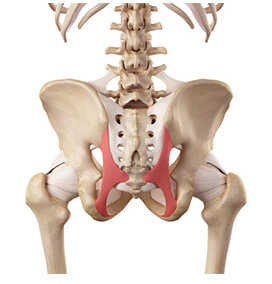

神経反射により仙骨・腸骨・背骨が瞬間的に矯正できます

瞬時に骨盤から順に椎骨が矯正されるので、関節由来の疼痛除去には大きな効果があります。

骨盤矯正に関して驚いたのは、仙結節靭帯をほんのすこし捻るだけのソフトなアプローチでガチガチに固まった脊柱起立筋を瞬時に緩め、痛みを取り除くことができることです。

私が受けた手技はカイロ界ではローガンベーシックと呼ばれている手技を三浦先生が改良したものです。これは仙結節靱帯にやさしくアプローチすることで、重心の左右差を矯正し自然と脊柱周りの筋硬結が緩んでいく不思議な手技です。施術者と被験者ともに筋肉がやわらかくなって痛みが取れるのを実感できるので、臨床でとても使いやすいと思います。

親指を使って仙結節靭帯を少しひねるだけで、腸骨・仙骨・背骨をすべて矯正することができるのです。

信じられないですか?でもこれは本当のことです。

このテクニックで仙結節靭帯にアプローチすると、ゴルジ腱器官の筋肉の弛緩作用によって、ガチガチに固まっていた脊柱起立筋と殿筋が一気に緩み始め、仙骨から腰椎、胸椎と背骨が下から順番にクルクルっと矯正されていきます。

さらに神経の反射によって、仙結節靭帯と交わっている後仙腸靭帯まで勝手に緩み、腸骨の歪みも自然と矯正されるのです。